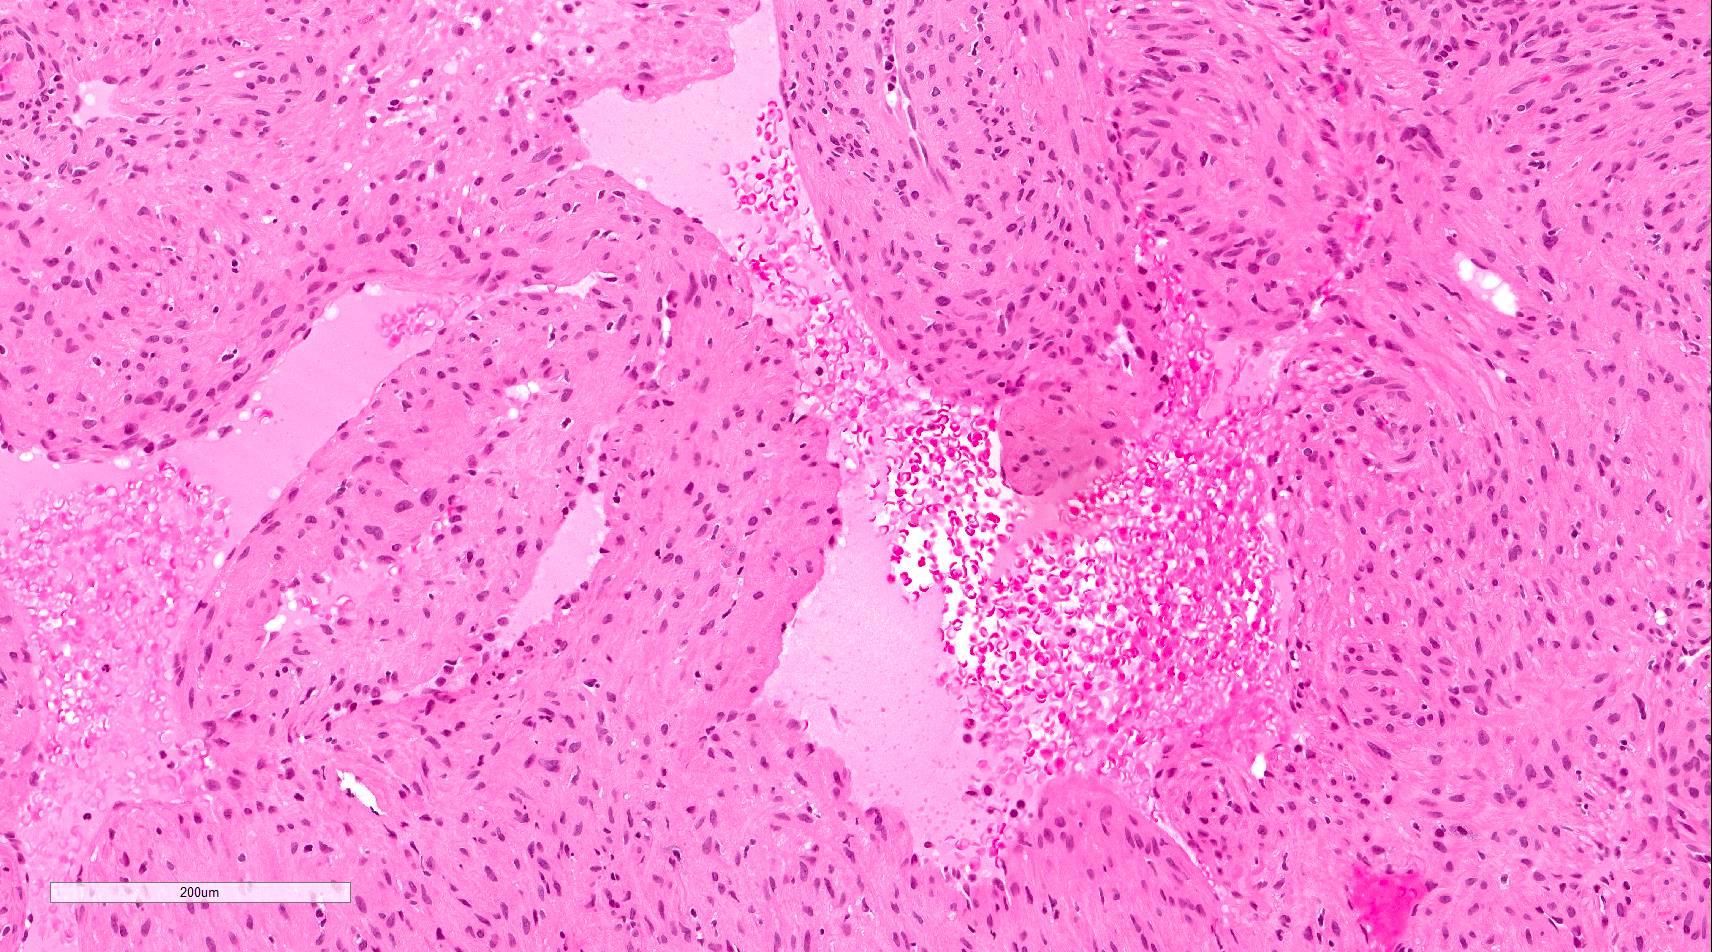

Microscopic (histologic) description

- Encapsulated proliferation of eosinophilic smooth muscle cells with minimal nuclear pleomorphism

- Rounded or slit-like veins with muscular walls present within the tumor (J Cutan Pathol 2017;44:342)

- Tumors can further be classified into 3 subcategories, first described by Morimoto et al:

- Solid type: smooth muscle bundles surround numerous small slit-like channels

- Cavernous type: dilated vascular channels, the walls of which are difficult to distinguish from the intervascular smooth muscle

- Venous type: thick walled vessels that are easily distinguished from the intervascular smooth muscle

- Epithelioid and pleomorphic variants are reported in a few cases

- Epithelioid type: composed of cells with round to oval nuclei and a moderate amount of finely granular eosinophilic cytoplasm with occasional vacuoles (Am J Dermatopathol 1998;20:213)

- Pleomorphic type: marked nuclear pleomorphism but only rare or absent mitoses (Am J Dermatopathol 2000;22:268)

- Calcification and marked degeneration, including hyalinization and myxoid changes, may be present (J Cutan Pathol 2017;44:342, J Ultrasound Med 2019;38:1201)

- Fat can be seen in a few cases; not to be mistaken for angiomyolipoma (Cancer 1984;54:126)

Microscopic (histologic) images

Contributed by Ohoud Aljarbou, M.D., Jijgee Munkhdelger, M.D., Ph.D. and Andrey Bychkov, M.D., Ph.D.

A. Angioleiomyoma. A mixture of smooth muscle bundles arranged in small fascicles and intervening vascular channels is noted. The concentric perivascular spindle cell proliferation which is characteristic for myopericytoma is absent. There are no glomus cells seen. Adipocytes are not seen in this image, which makes angiomyolipoma less likely.